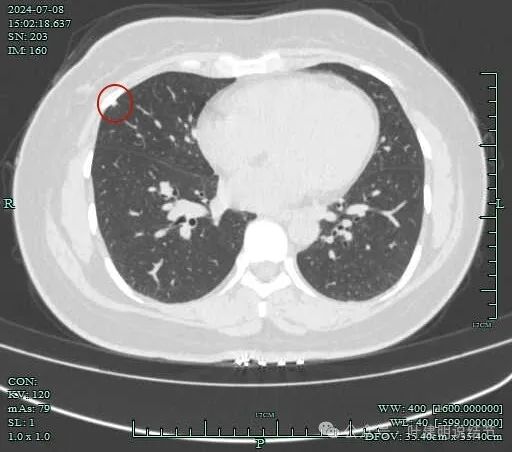

再看2024年7月份的影像:

病灶纵隔窗上是软组织影,表面不平,形态不规则。上腔静脉旁有肿大淋巴结。

病灶膨胀性不明显。

邻近支气管有扩张,表面不平,分叶明显。

肺窗上见与上腔静脉紧贴着,病灶边缘稍显模糊。

病灶边上不清爽。

病灶有毛刺与小棘突征,有邻近细支气管扩张,表面不平,膨胀性不明显。

毛刺征明显,灶边细支气管扩张。